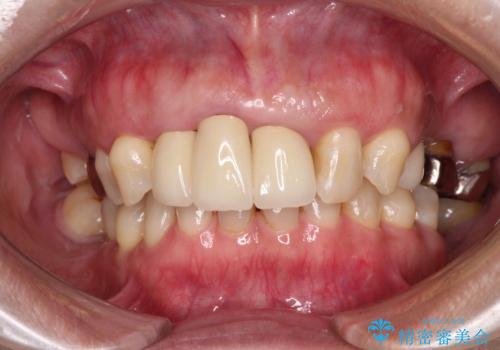

歯肉の位置は変更できないため、露出している歯根をクラウンで覆い隠すと歯が長く見えることを事前にお伝えしておりました。

真ん中2本は治療前よりも短めに仕上げることで、極端に長い印象を避けることができました。